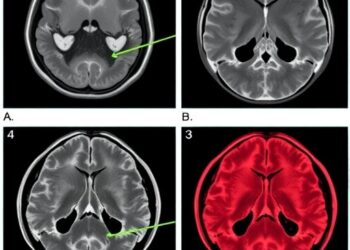

In a groundbreaking study published in BMC Cancer, researchers at Tangdu Hospital, Air Force Medical University, have presented a comprehensive ...